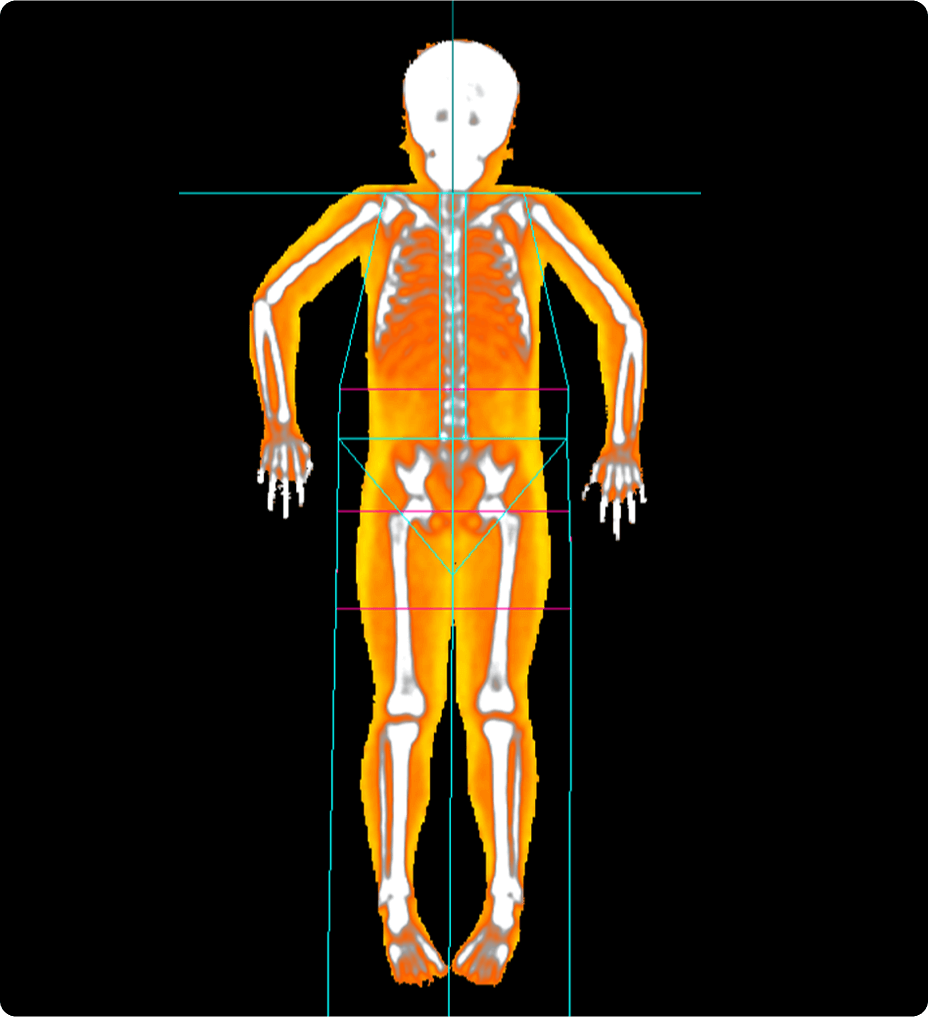

• Zero-click bone segmentation for head, neck, and other

anatomy.

• Automated detection of aorta an illiacs with auto labeling of vessels.